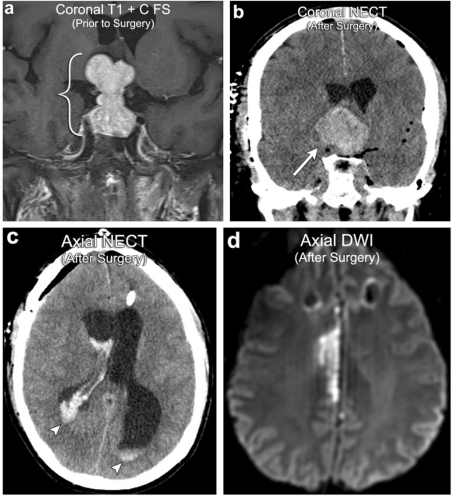

案例2:垂体大腺瘤术后出血 、梗塞

52岁男性,垂体大腺瘤(括号)。大体切除术后的MR显示残留腺瘤的出血扩大与垂体卒中(箭头)一致。还有脑室间的出血扩展(箭头)。随访MRI显示由于垂体腺瘤出血增大后的右侧大脑前动脉受占位效应导致右侧大脑前脑动脉(ACA)供血区域梗死。